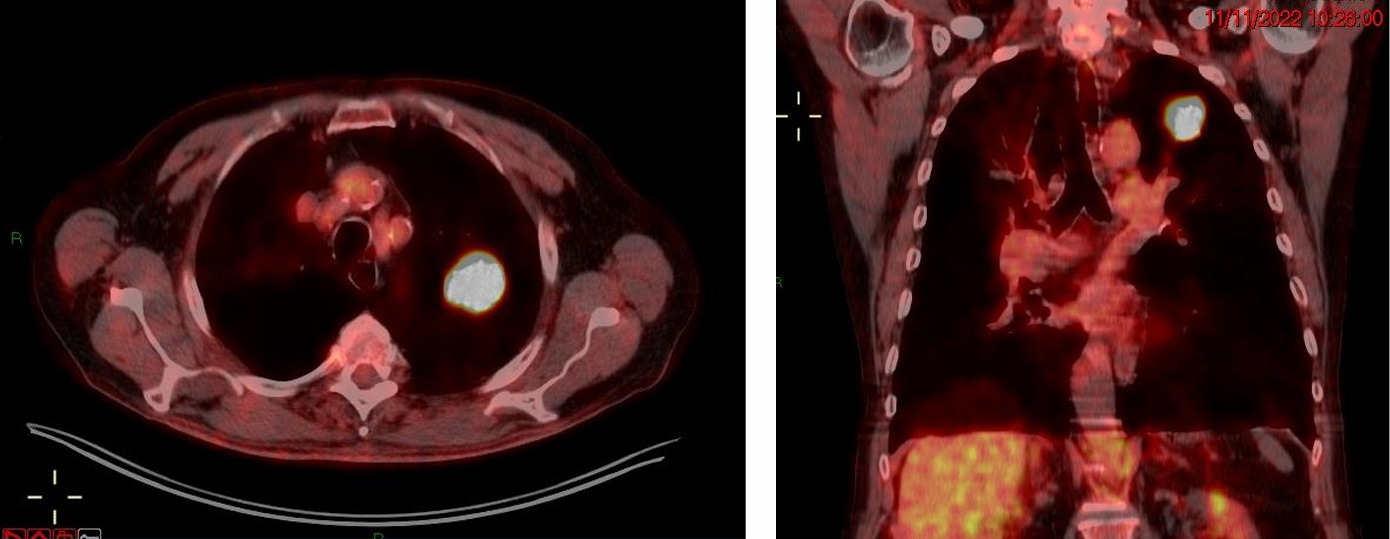

影像学评估

CT:左肺上叶尖段25mm结节,毛刺征阳性;双肺弥漫性肺气肿;右上肺巨大肺大疱(10.7cm),局部压迫邻近组织。

FDG-PET/CT(2022-11-11):结节SUVmax为5.8,未见淋巴结或远处代谢异常。